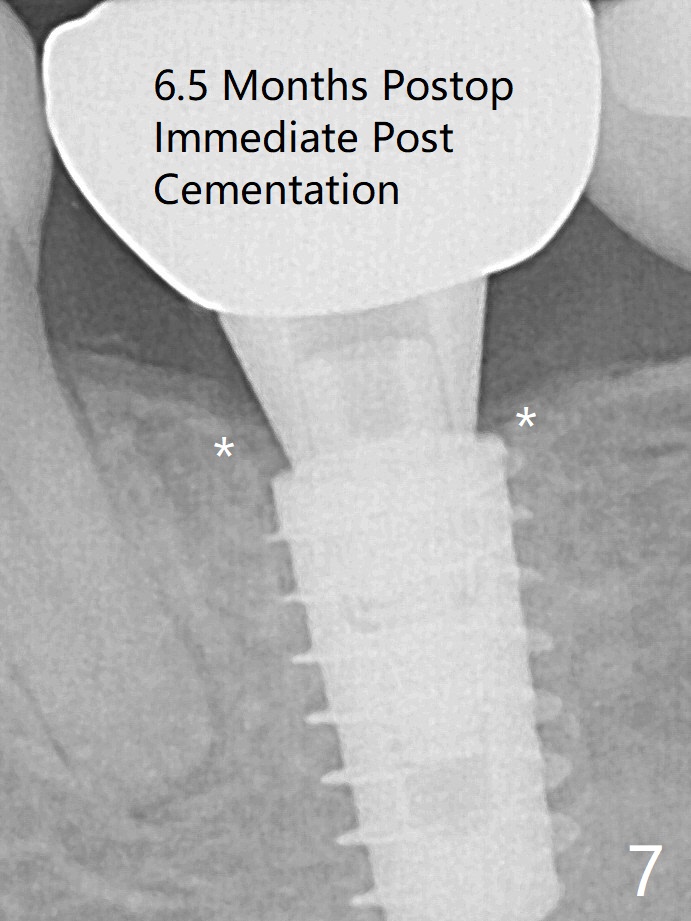

In contrast to #2 implant, the insertion torque of a 5x9 mm implant at #18 (Fig.1) is less than 10 Ncm because of depth difference between 2 implant systems. The design is for 5x10 mm. In fact each drill has its inherent 1.2 mm long tip. The 8.5 mm drilling depth is enough for 9 mm implant. The 2nd potential problem is that the implant may truncate a branch from the Inferior Alveolar Canal to the distal root of the 1st molar (Fig.2 (original design)). Ideally the implant should be placed distal and tilted mesial and short in length (Fig.3 (design to be improved)). A smaller implant may also help. A layer of new bone forms on the top of the implant 3 months postop (Fig.4 *). It is removed with surgical handpiece. After use of 5.6 mm profile drill, a 6x4 mm healing abutment is placed with minimal clearance from the mesial crest (Fig.5 *). A month later, a 5x4(3) mm pair abutment is seated apparently completely (Fig.6). A crown is delivered nearly 6.5 months postop (Fig.7 (mesial contact light)). The implant is subcrestal (*).